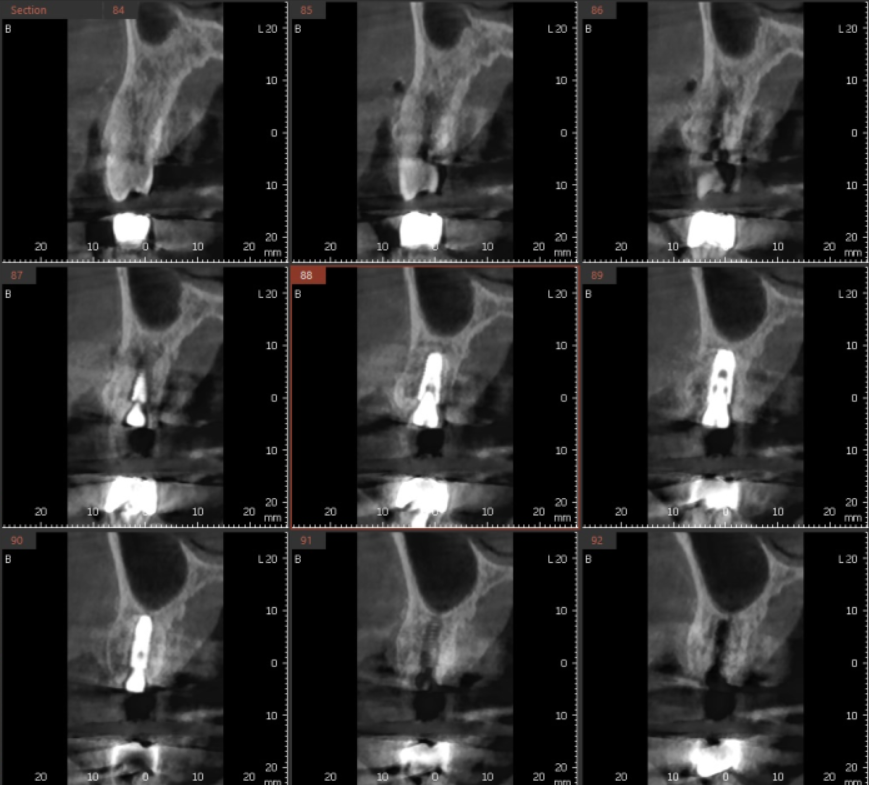

23.07.11

발치 후 당일 임플란트 식립 후 사진입니다.

디지털 장비를 이용하여

수술 중간중간 재차 확인

안전하게 발치 후 당일 임플란트가 가능했습니다.